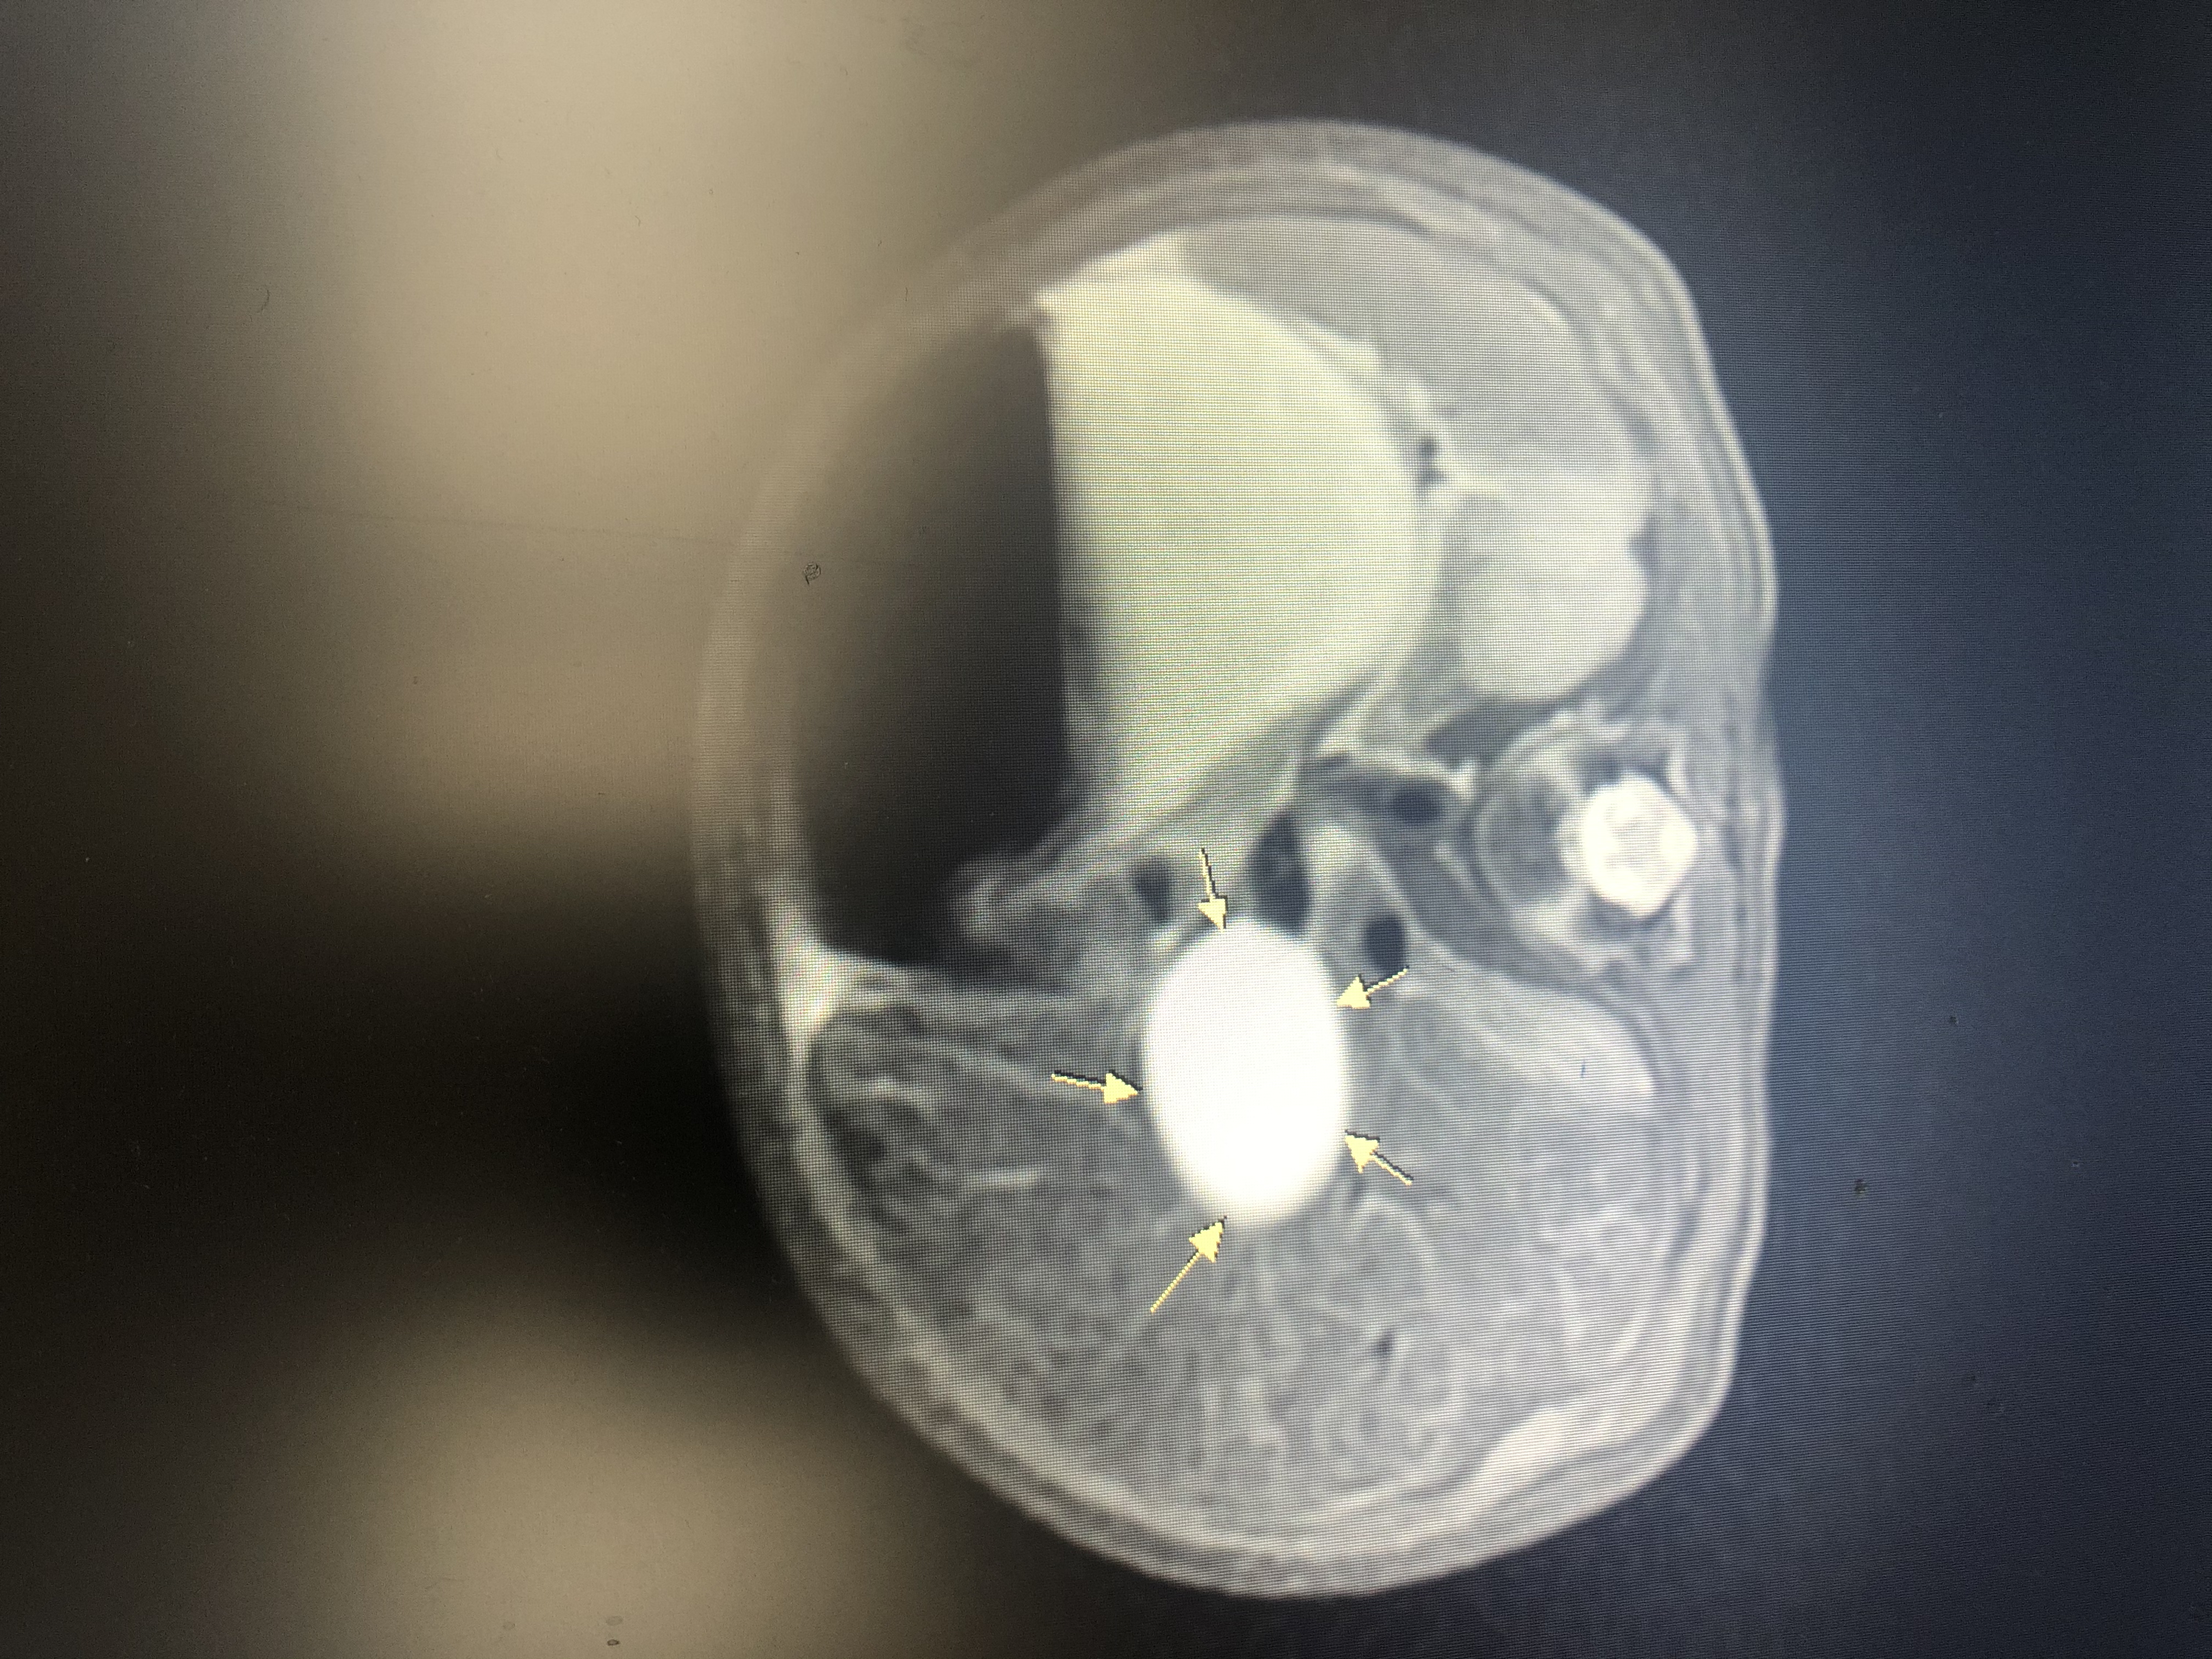

箭头指向胆总管,直径达25.68mm,正常直径只有3-4mm

小宝是平阳人,4月10日在附二院南浦院区出生,胎龄38周,体重3870克。他的疾病在妈妈怀孕24周时就通过产前检查发现了,所以出生后直接住院。经过检查,他的囊肿大小为32*17毫米,有一个鸡蛋大小。4月23日,小宝接受了3个多小时的手术。

“这个囊肿,并不是说孩子身体长了什么瘤,而是因为胆总管远端梗阻以后,胆汁排不下去,就像气球一样鼓了起来。囊肿慢慢变大后会破掉,届时会损害肝功能,甚至有癌变的风险。”林进汉说,手术难度不小:孩子特别小,胆总管壁很薄,医生要用比头发丝还细的线,将肠管和胆总管缝合衔接起来;肠管粗一点,胆总管很细,无法口对口“端端吻合”,医生就在肠管的一侧另打一个小口,做“端侧吻合”;衔接的“通道”,既要打通,又不能太狭窄,“接口”处千万不能漏,否则漏出胆汁就要行二次手术,所以医生光“接口”就花了一个多小时……好在,经过医生的努力,手术非常顺利,以后孩子有一段肠管将代替胆总管的功能发挥作用。手术做好半个月,小宝达到出院标准。